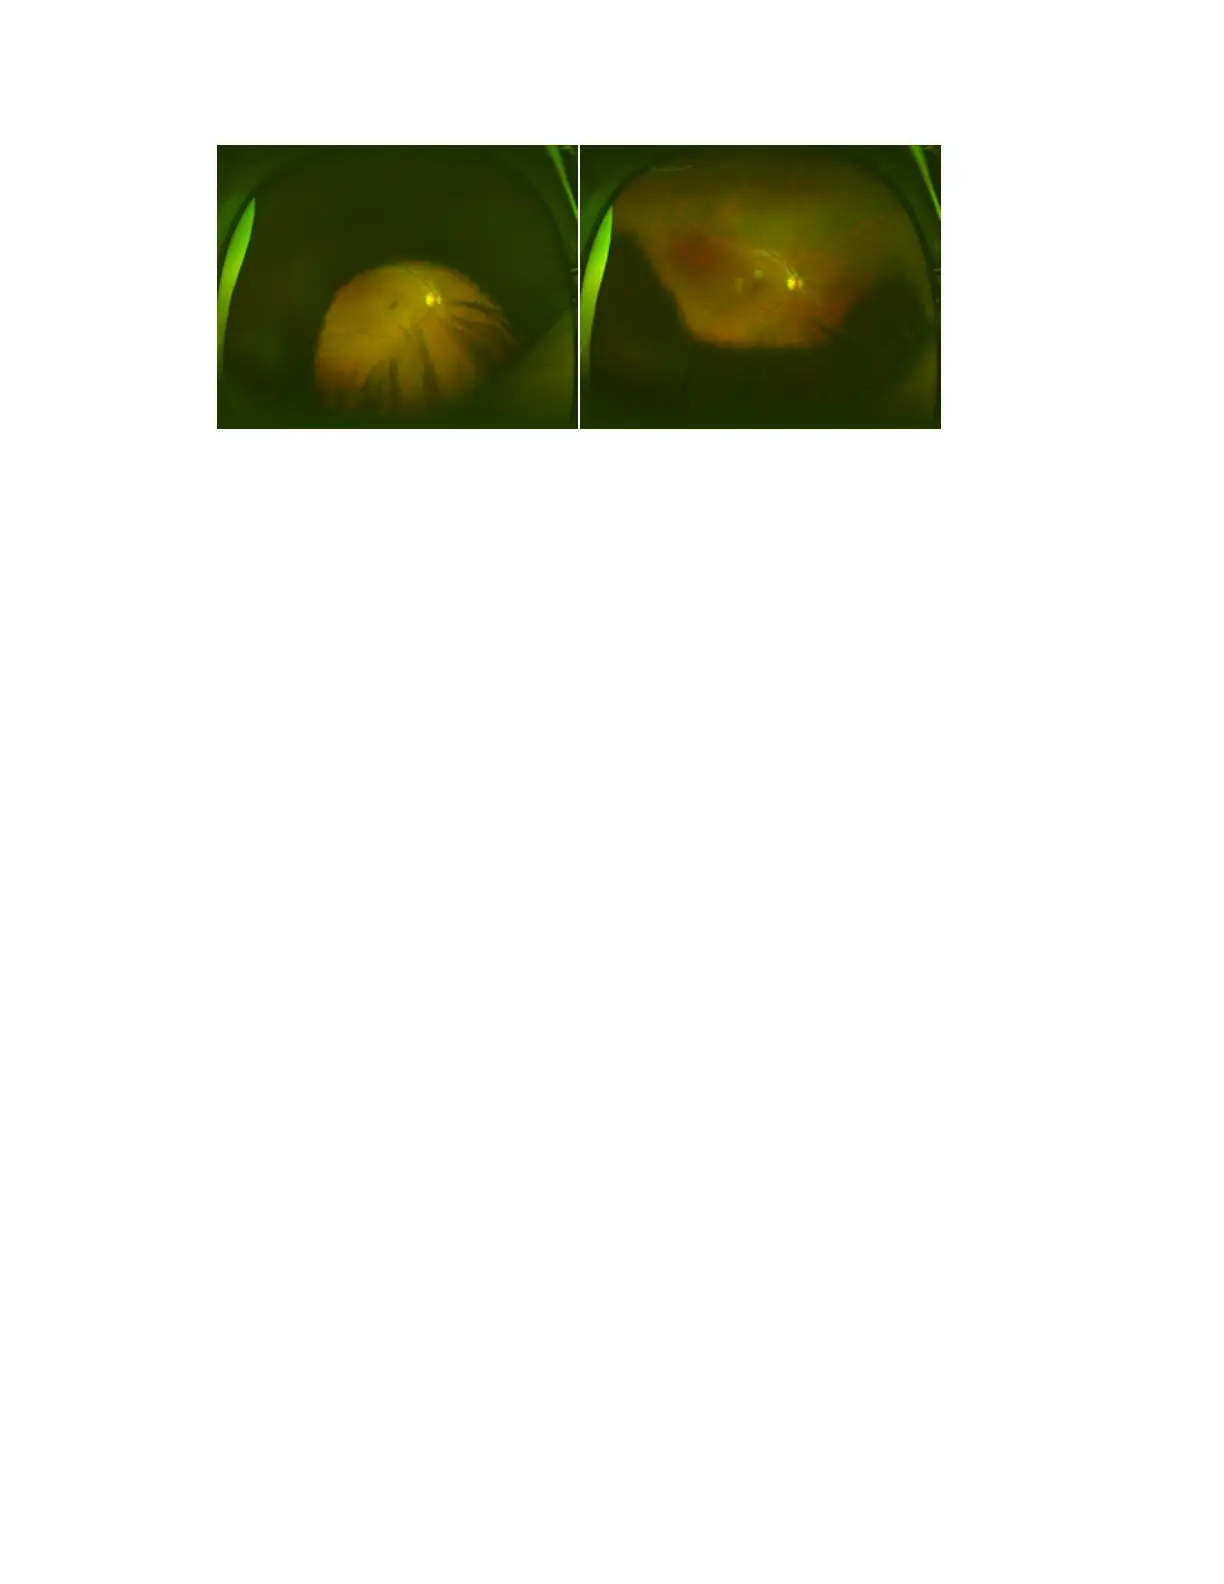

Patient too high Patient too low

Minimizing lids and lashes in images

In some patients, images may be obscured by the patient's lids and lashes. You should follow your

practice procedures to minimize lids and lashes in images.

In some cases the amount of lid and lash can be minimized by gently lifting the patient's eyebrow.

1. With clean hands, place your thumb below the patient's eye and your forefinger on the brow line.

2. Gently open the eye a little further. Just lifting the upper lid may pull the lower lid further into the

image.